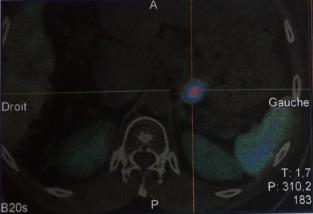

Multiple endocrine neoplasia type 1 (MEN1) is a rare disease, defined as a tumor developing in at least two endocrine glands including the anterior pituitary gland, the parathyroid glands and the duodenopancreatic endocrine tissue. This disorder, inherited in an autosomal dominant pattern, is caused by mutations in the MEN1 gene encoding the tumor suppressor menin and located on chromosome 11q13. However, sporadic cases account for 8-14%. The first endocrine lesion may be solitary in approximately 75% of cases. However, all major alterations can be inaugural. We here report a case of multiple endocrine neoplasia type 1 revealed by aggressive somatoprolactinic pituitary adenoma which didn't respond to conventional treatment. The detection of primary hyperparathyroidism as well as neuroendocrine tumor of the pancreas seven years later make this a very particular case. Therapeutic options are discussed within the multidisciplinary team specialized in endocrine diseases.

多发性内分泌腺瘤1型(MEN1)是一种罕见疾病,定义为在至少两个内分泌腺发生肿瘤,这些内分泌腺包括垂体前叶、甲状旁腺和十二指肠胰腺内分泌组织。这种疾病以常染色体显性模式遗传,由位于11q13染色体上编码肿瘤抑制因子menin的MEN1基因突变引起。然而,散发病例占8 - 14%。在大约75%的病例中,首个内分泌病变可能是孤立性的。然而,所有主要病变都可能是首发的。我们在此报告一例由侵袭性生长激素泌乳素型垂体腺瘤引发的多发性内分泌腺瘤1型病例,该垂体腺瘤对传统治疗无反应。七年后检测出原发性甲状旁腺功能亢进以及胰腺神经内分泌肿瘤,使该病例非常特殊。在专门从事内分泌疾病的多学科团队中讨论了治疗方案。